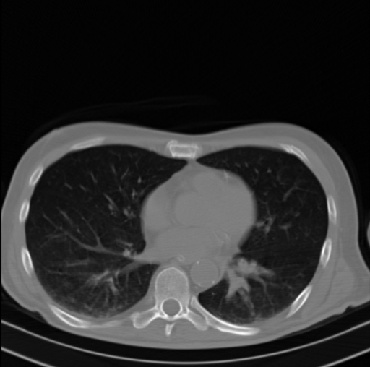

Early and reliable COVID-19 diagnosis based on chest 3-D CT scans can assist medical specialists in vital circumstances. Deep learning methodologies constitute a main approach for chest CT scan analysis and disease prediction. However, large annotated databases are necessary for developing deep learning models that are able to provide COVID-19 diagnosis across various medical environments in different countries. Due to privacy issues, publicly available COVID-19 CT datasets are highly difficult to obtain, which hinders the research and development of AI-enabled diagnosis methods of COVID-19 based on CT scans. In this paper we present the COV19-CT-DB database which is annotated for COVID-19, consisting of about 5,000 3-D CT scans, We have split the database in training, validation and test datasets. The former two datasets can be used for training and validation of machine learning models, while the latter will be used for evaluation of the developed models. We also present a deep learning approach, based on a CNN-RNN network and report its performance on the COVID19-CT-DB database.